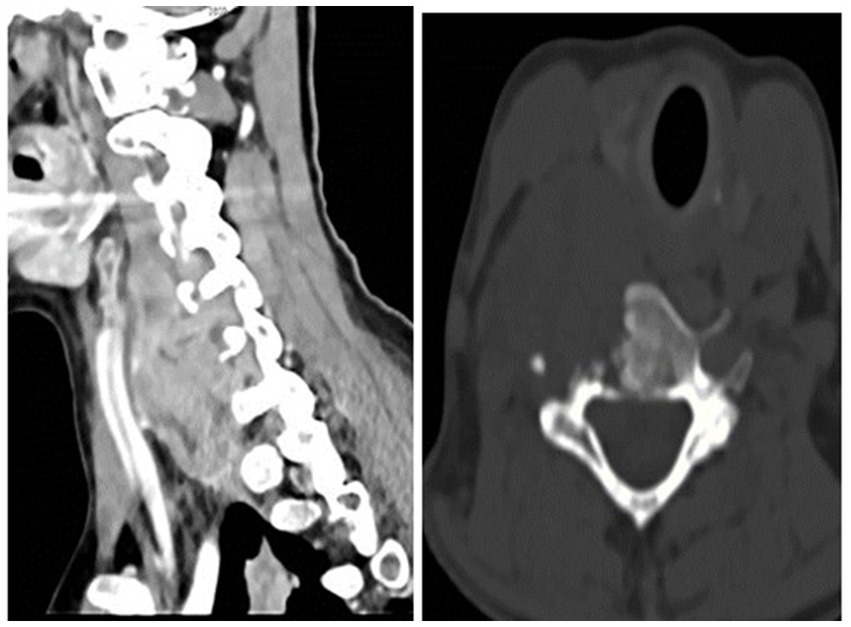

Radiologists performed multiple diagnostic imaging studies that revealed lung, liver, colon, and peritoneal metastases. There was a right-sided neck colliquative mass (most likely metastasis), 75 × 40 × 35 mm in diameter, with C5 and C6 vertebral destruction and propagation to the spinal canal (Figure 4).

Figure 4

Right-sided neck mass.